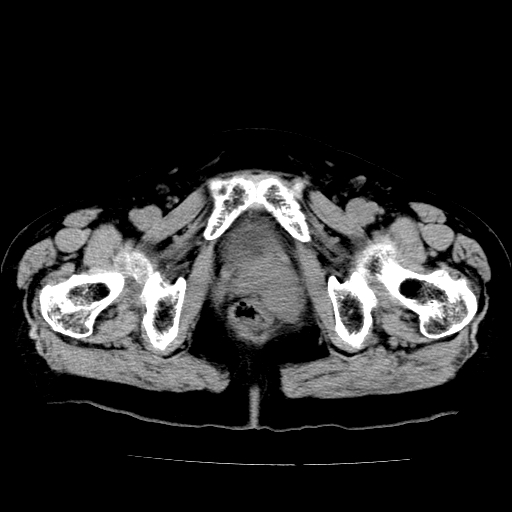

女,73岁,阴道流血一周。

宫颈不规则增大;结合临床考虑宫颈癌。建议作mri检查

1\\老年妇女突发阴道流血,常见病考虑宫颈癌.本病例宫颈部显示形态不规则,密度欠均匀,支持考虑宫 颈癌,建议mri 或阴道超声坚持

2\\但是盆腔两侧尚未见到明显肿大淋巴结等转移征象

宫颈不规则增大,左后方可见结节状突起.支持宫颈癌.

宫颈壁明显增厚,左侧为甚,宫颈癌待排,建议宫颈涂片细胞学检查。

宫颈不规则增大,周围脂肪间隙毛糙,结合临床考虑宫颈癌,盆腔内未见肿大淋巴结。